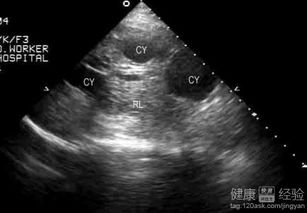

超声检查:首选影像学检查,可清晰显示囊肿的大小、数量、位置及内部结构。

肝囊肿是指在肝脏内形成的充满液体或半固体内容物的囊状结构,这些囊肿通常壁薄、内壁光滑,大小不一,小的直径仅几毫米,大的可达数厘米甚至更大,单个肝囊肿较为少见,多数患者为多发性肝囊肿。